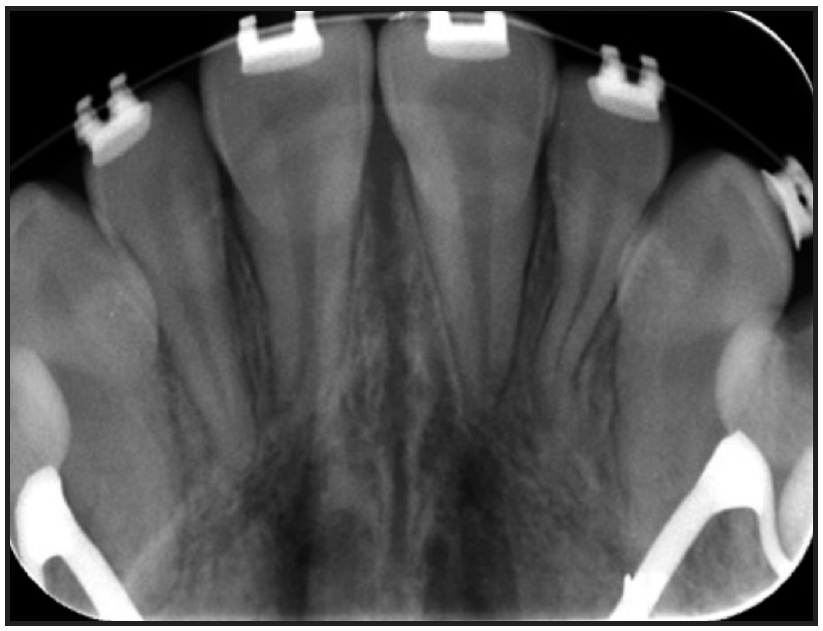

A nickel titanium Memoria Leaf Spring Activated Expander was placed (Fig. 7) and activated 10 times at each monthly appointment for six months, until about 6.5mm of intermolar expansion had been obtained (Fig. 8, Table 2). The expander was then made passive by adding flowable composite to stabilize the springs. A maxillary impression was taken and digitized to evaluate the molar angulation changes (Fig. 9). The occlusal radiograph revealed no noticeable sutural disruption (Fig. 10).

Fig. 10 Case 2. Occlusal radiograph showing no noticeable sutural disruption after expansion.